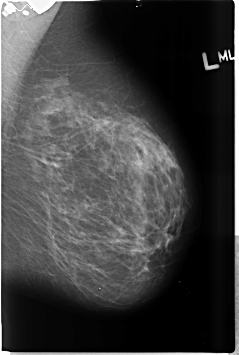

B_3488_1.LEFT_MLO

LEFT_MLO LINES 4608 PIXELS_PER_LINE 3104 BITS_PER_PIXEL 12 RESOLUTION 50 NON_OVERLAY